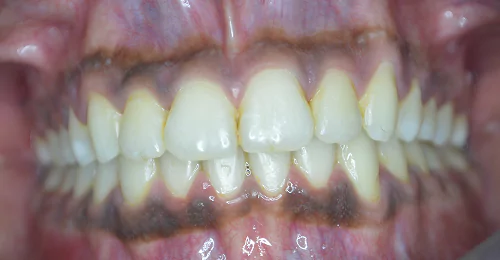

Orthodontic Case – IV

(Case Done by Dr. Sonali Deshmukh M.D.S. / Orthodontist )

Correction of Open Bite

Pre Treatment